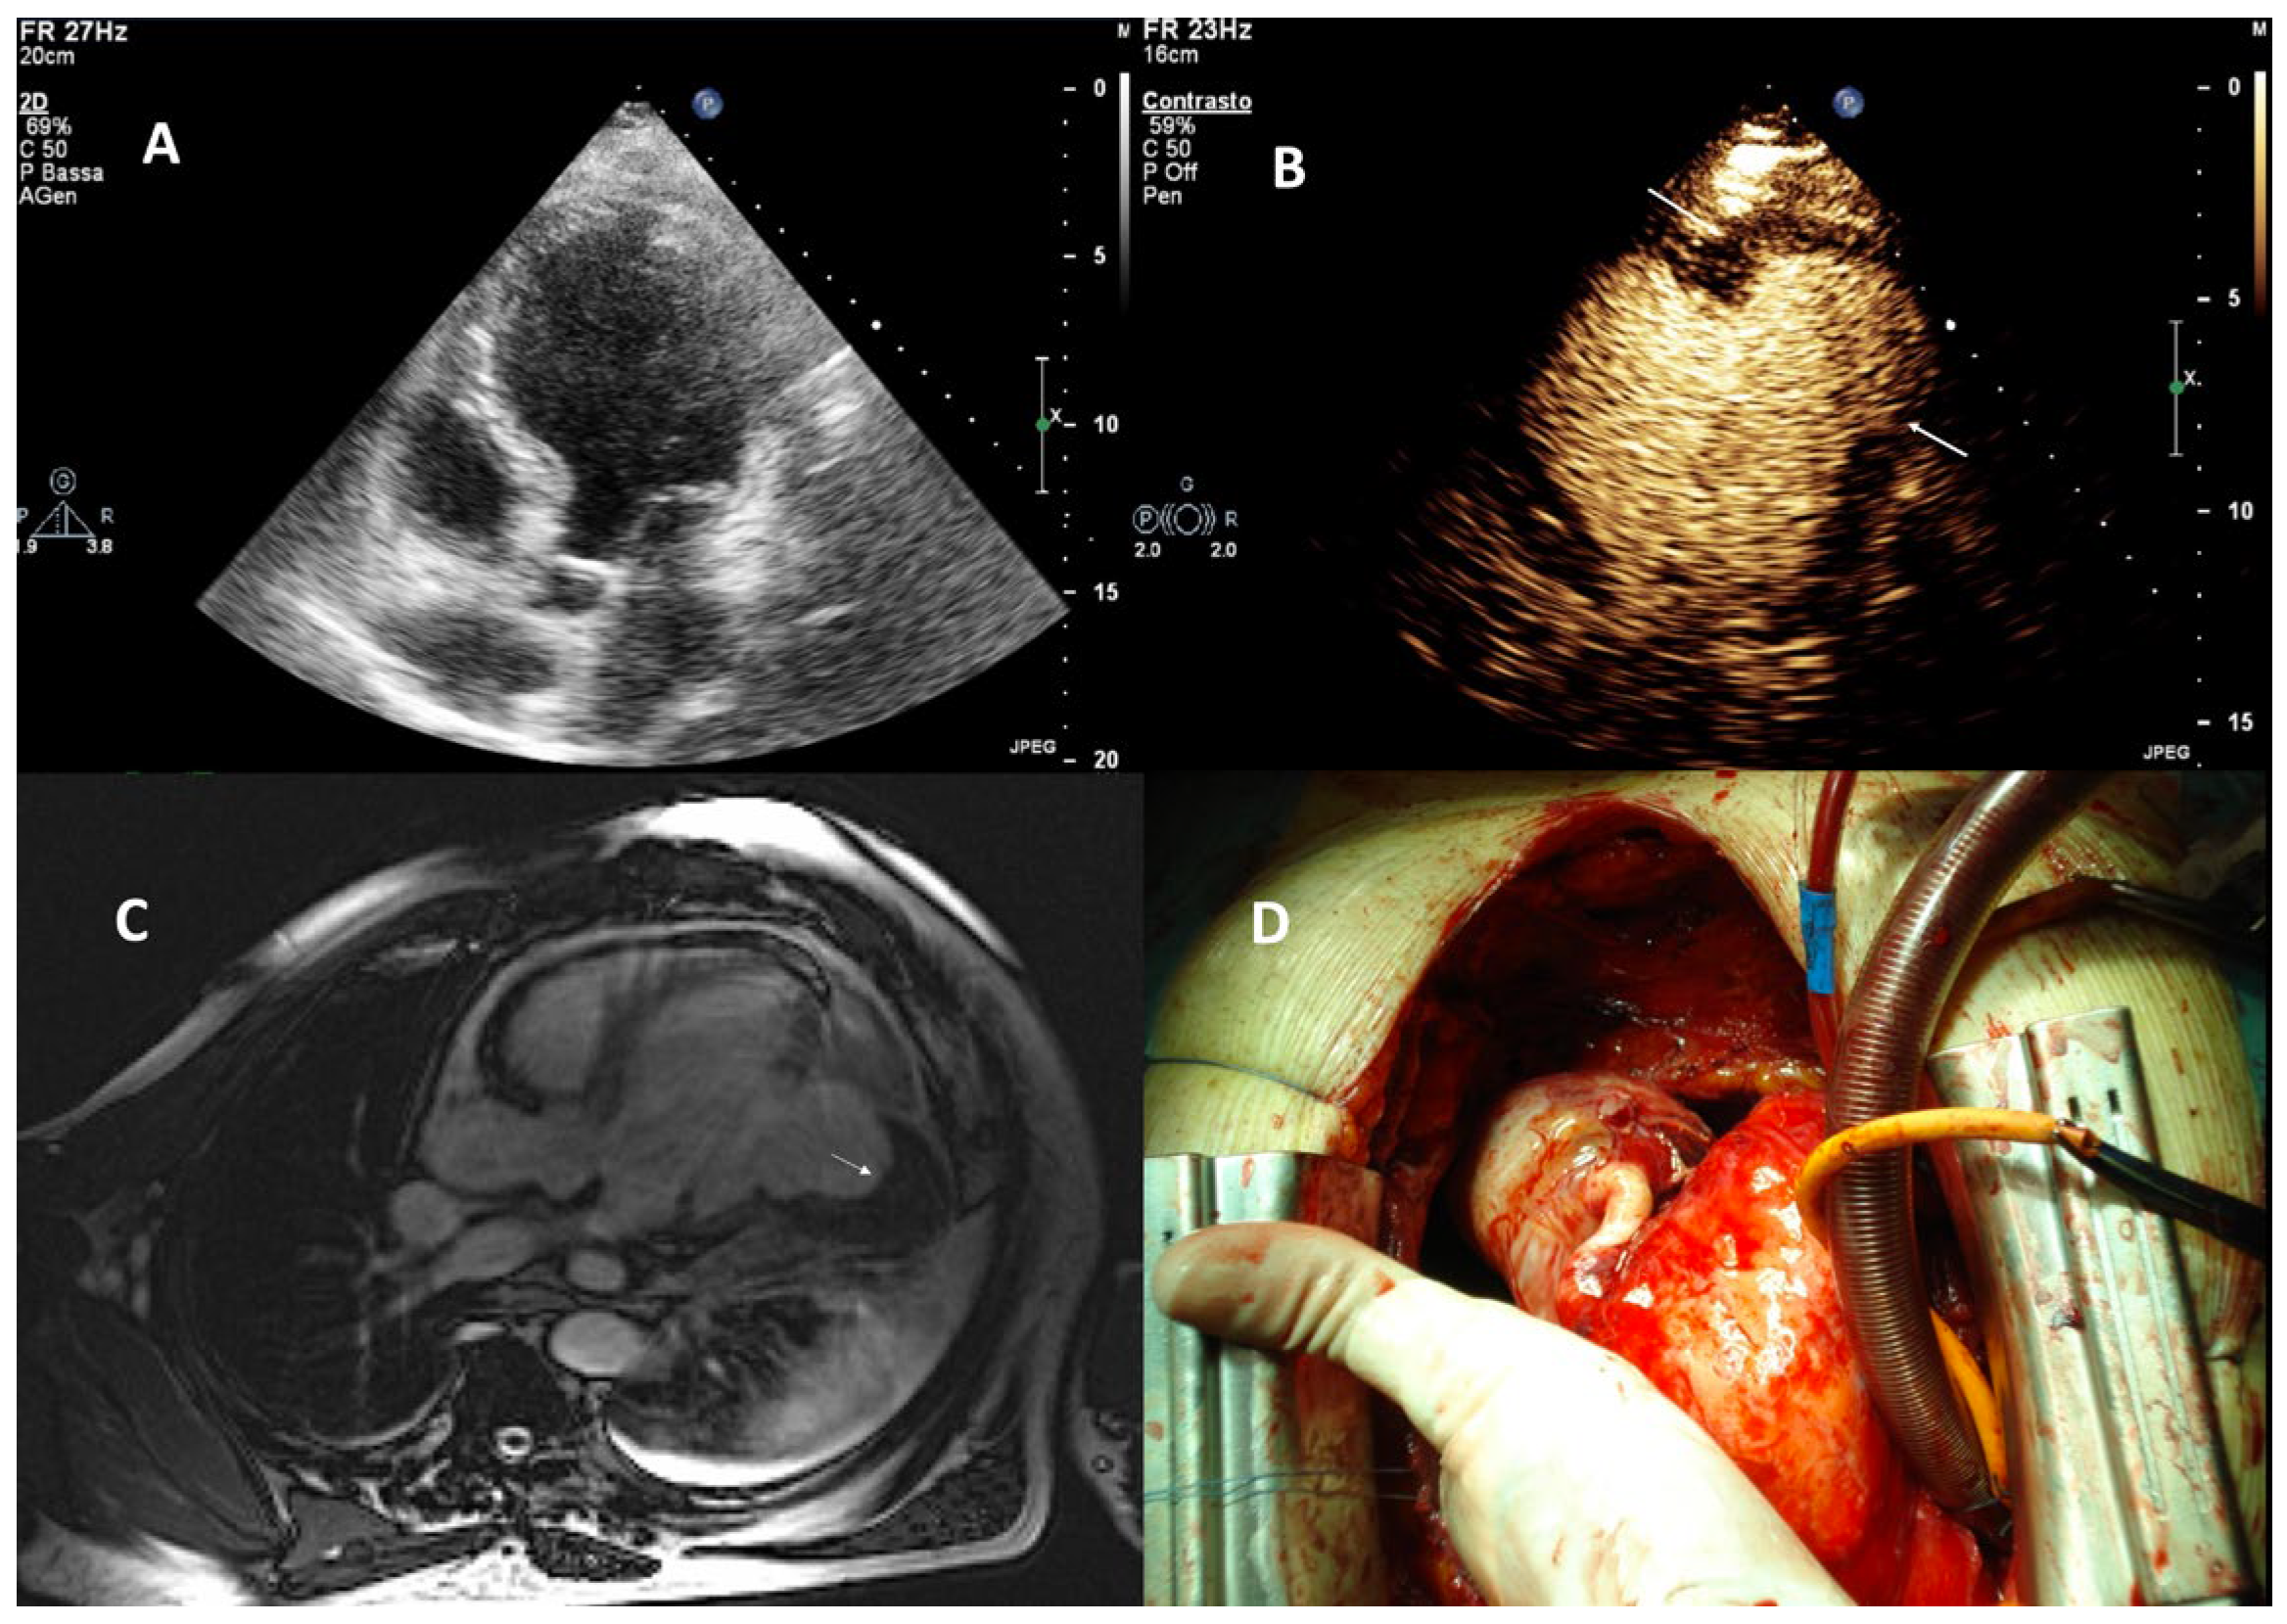

| Thrombi |

| Imaging method | Low-MI-contrast-specific imaging and intermediate-MI-contrast-specific imaging |

| Imaging planes | standard apical views additional zoomed views sweeps through the region of the suspected thrombus |

| Sector depth/width | Entire LV + 1/3 LA to assess global/regional LV function, zoomed views of the region with the suspected thrombus |

| Focus | At the depth of the suspected thrombus |

| Gain | Adjust to avoid obscuring the thrombus by intensive opacification of the cavity |

| Contrast application | bolus injections |

| Typical findings | 1. echofree mass 2. present in two different imaging planes 3. lump or laminar shape different from trabeculations’ documented size (two orthogonal diameters in at least one of the views), location, type (laminar vs. lump, single vs. multiple), surface (smooth vs. irregular) and mobility |

| DD tumor vs. thrombus | Opacified (vascularized) masses are suggestive of tumors; the vascularization can be demonstrated with myocardial perfusion imaging. CAVEAT: There are malignant tumors which appear avascular on CEUS. Tumors often are attached to normal myocardium. |

| Alternative imaging | Thrombi: Cardiac MRI when contrast echo is not possible or non-diagnostic, cardiac CT when cardiac MRI is not available Tumors: MRI provides tissue characterization and should be performed unless there is typical myxoma (attached to the interatrial septum) |